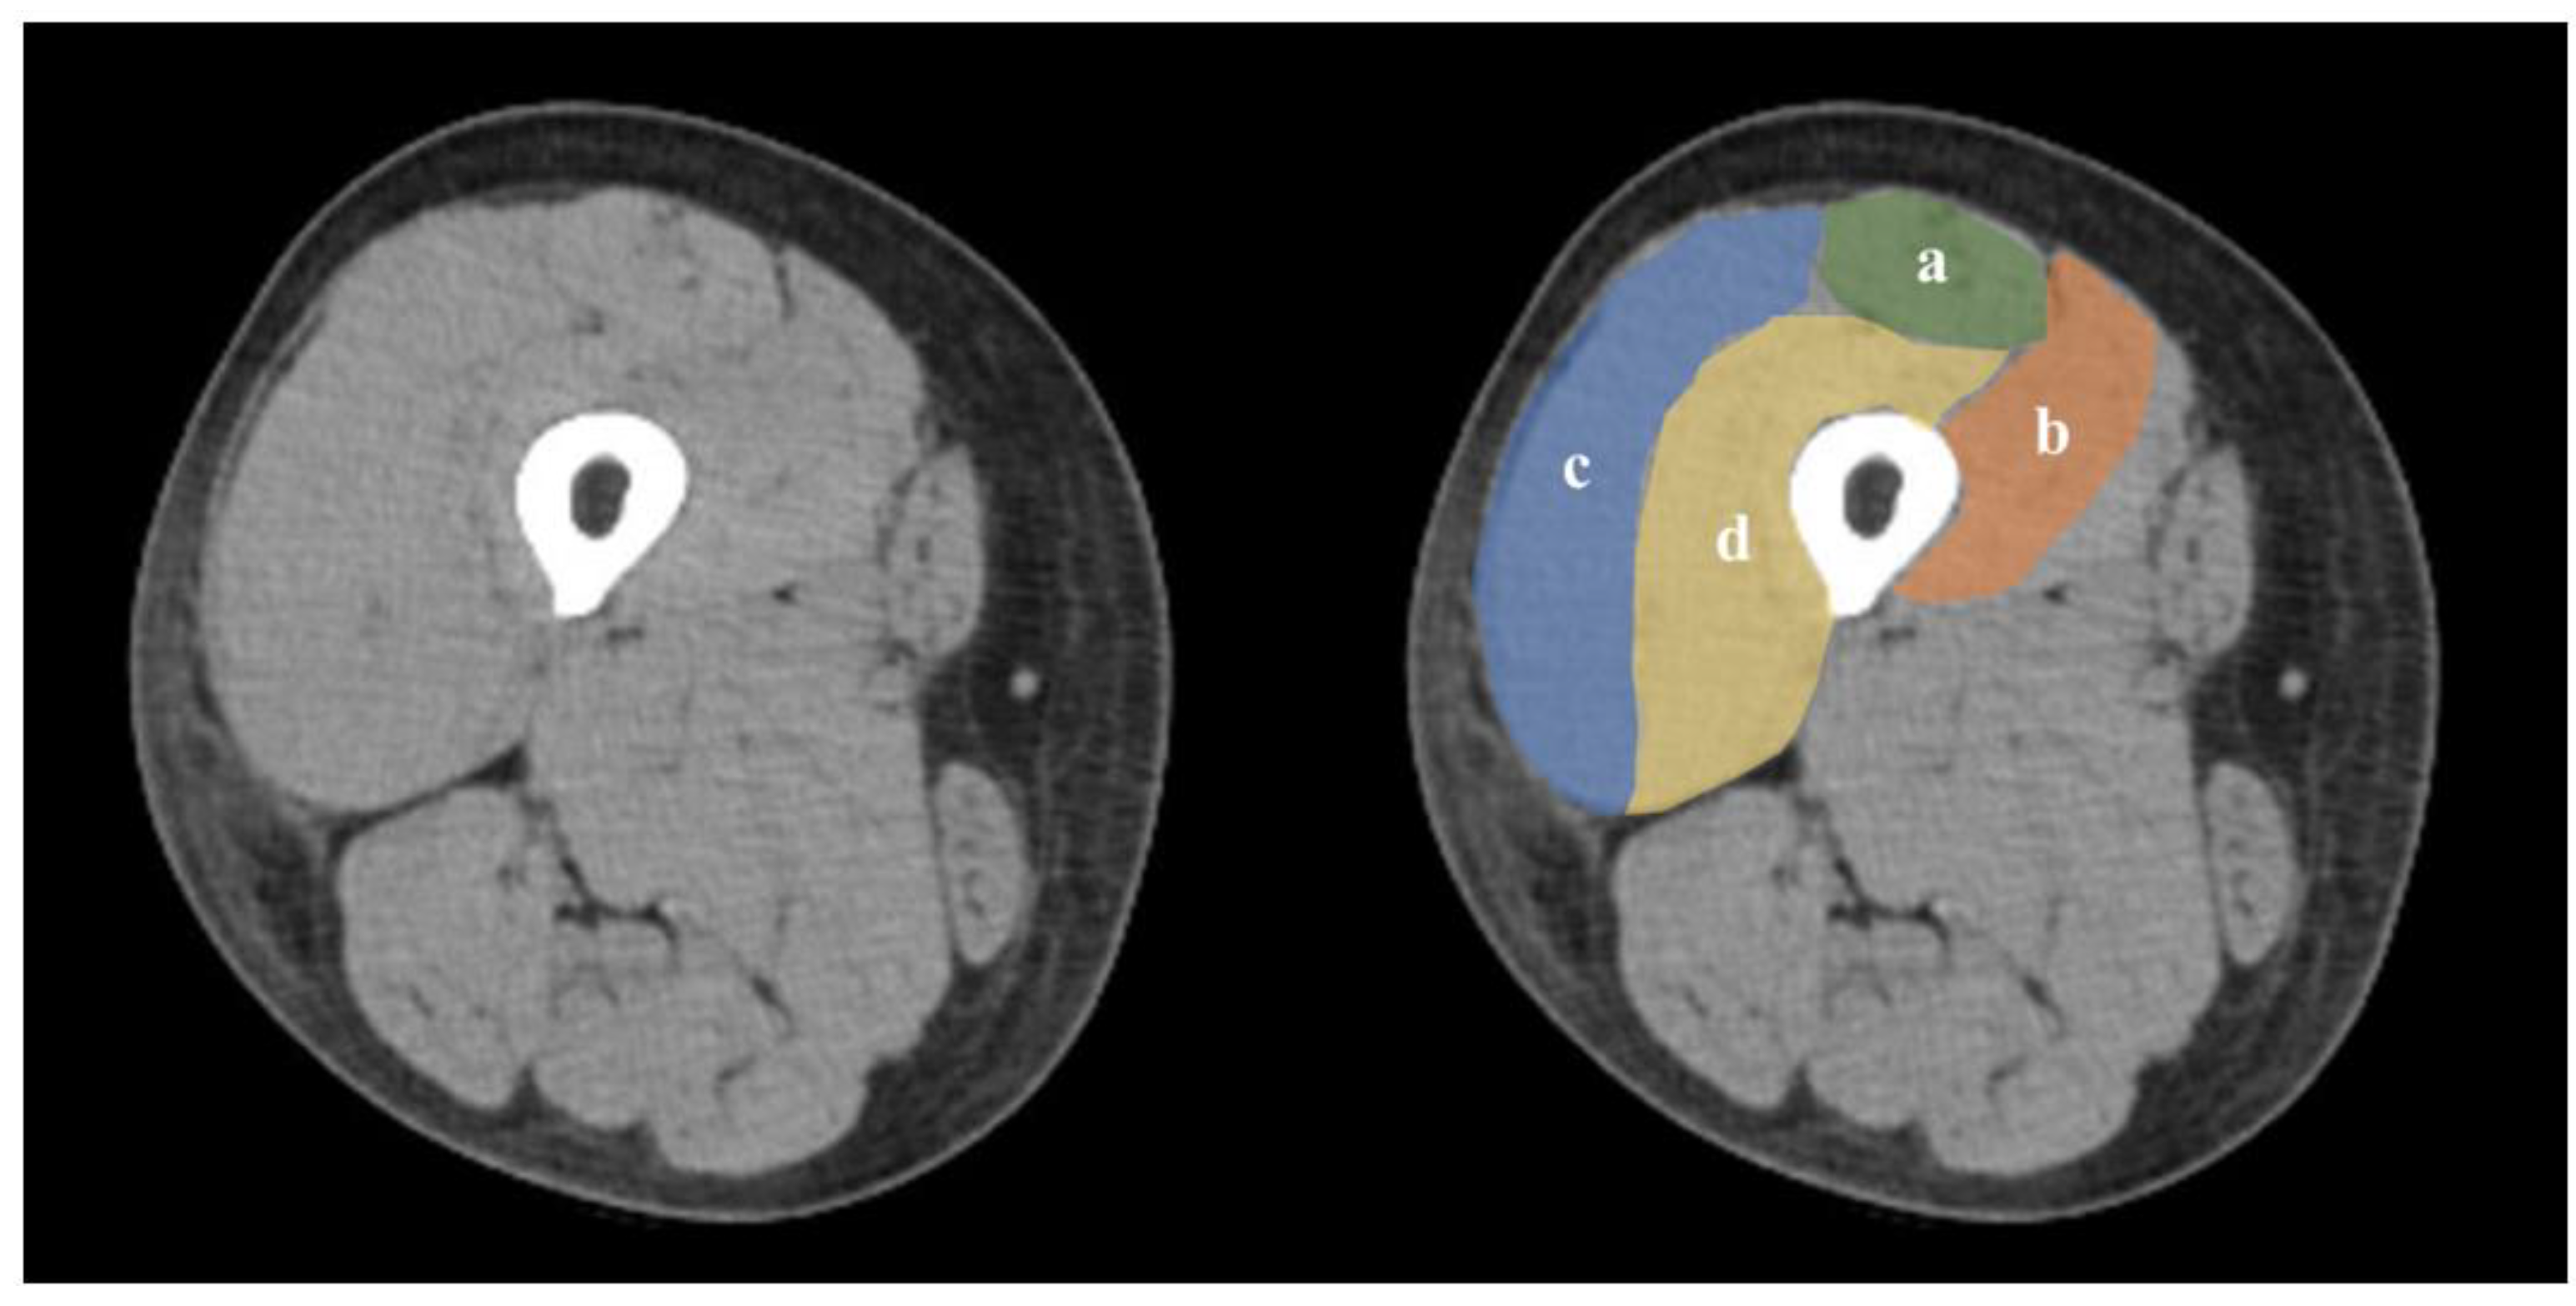

2.3. Assessment Variables

2.6. Skeletal Muscle Assessment

- Strandberg, S.; Wretling, M.L.; Wredmark, T.; Shalabi, A. Reliability of computed tomography measurements in assessment of thigh muscle cross-sectional area and attenuation. BMC Med. Imaging 2010, 10, 18. [Google Scholar] [CrossRef] [PubMed]